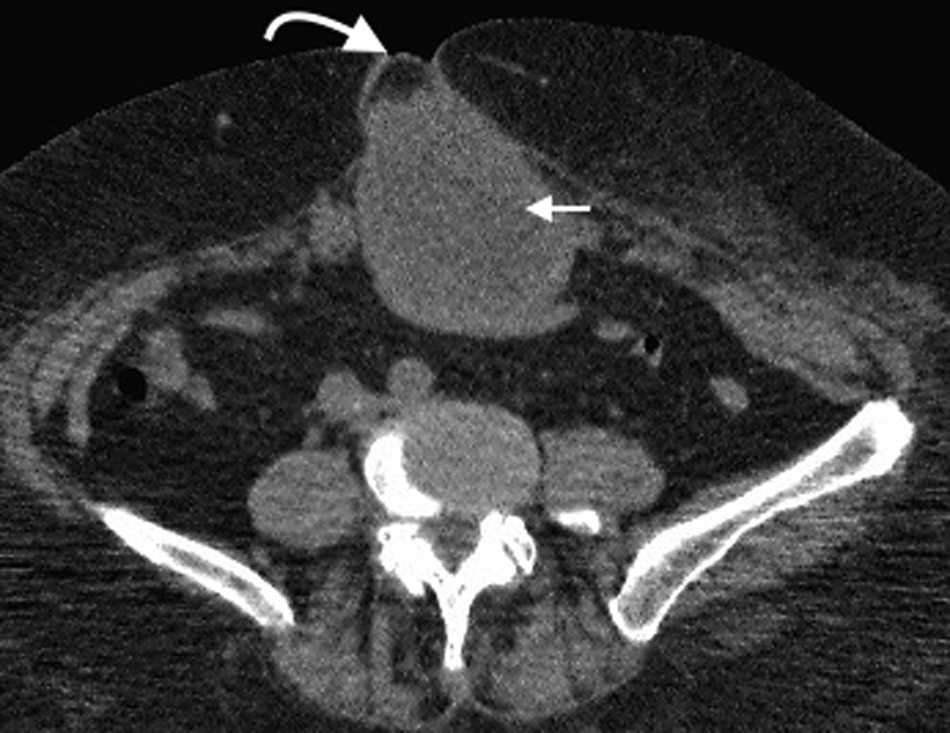

Hernia de Spiegel

Es una hernia ventral adquirida poco frecuente4. Ocurre por un defecto en la aponeurosis de los m??sculos oblicuo interno y transverso abdominal, y tiene una localizaci??n caracter??stica en la uni??n de las l??neas semilunar y semicircular o arqueada3. Es lateral al recto anterior del abdomen e inferior al ombligo, y casi siempre se encuentra justo por encima del punto en el que los vasos epig??stricos inferiores perforan la pared posterior de la vaina del m??sculo recto del abdomen1.

Su diagn??stico cl??nico no es f??cil porque esta hernia se extiende entre las capas musculares o fasciales de la pared abdominal anterior. El orificio herniario puede ser peque??o, dif??cil de localizar y tener grasa omental (fig. 5a), asas de intestino delgado (fig. 5b) o implantes metast??sicos12 (fig. 6).